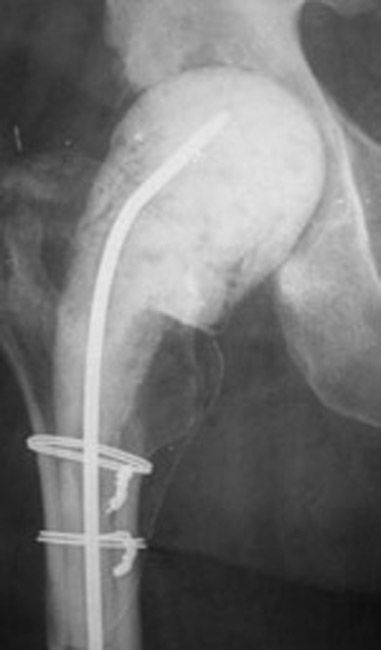

Background Prosthetic joint infection PJI of total hip THA or total knee arthroplasty TKA after dental procedures is uncommon and antibiotic prophylaxis remains controversial. Fevers night sweats and chills.

Symptoms of hip replacement infection after dental work. This is problematic in places like the gut gastrointestinal system where an altered microbiome can cause diarrhea abdominal pain malabsorption of nutrients and a host of other unwanted symptoms. Symptoms of Joint Infection. A small percentage of patients undergoing hip or knee replacement roughly about 1 in 100 may develop an infection after the operation.

Chronic infections may have very subtle presentations. One of the risk factors for developing an infection after a dental procedure is having artificial hardware in ones body. There is an estimated 05 to 1 risk of an infection following a hip replacement.

Developing an infection in and around a total hip or knee replacement is one of the most catastrophic complications that can occur. Increased stiffness and pain in a normally well-functioning joint. Symptoms of artificial joint infection.

Persons who have undergone joint replacement surgery are at risk for developing infections of their implanted joints. In acute infections there may be additional symptoms of swelling drainage of the joint and joint tenderness.